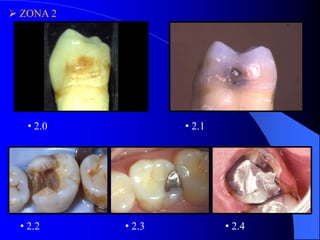

 ZONA 2

• 2.0

• 2.1

• 2.2

• 2.3

• 2.4